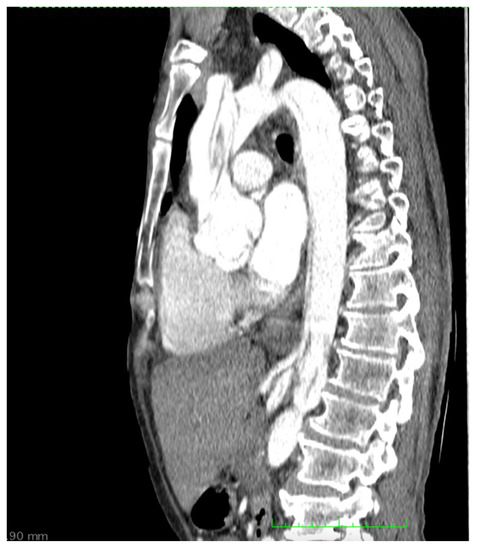

2. Case Report